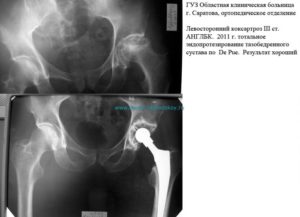

- Третья стадия характеризуется серьезными деструктивными поражениями сустава. Наблюдается атрофия мышц бедра, голени и ягодицы, что приводит к укорочению ноги на пораженной стороне, изменению центра тяжести и хромоте. Все это приводит к тому, что нагрузка на сустав еще больше увеличивается, а процесс его разрушения становится еще более интенсивным. Болевой синдром достигает максимальной интенсивности и мучит пациента даже ночью, в состоянии покоя. Эта стадия при отсутствии надлежащего лечения заканчивается для пациента инвалидностью.